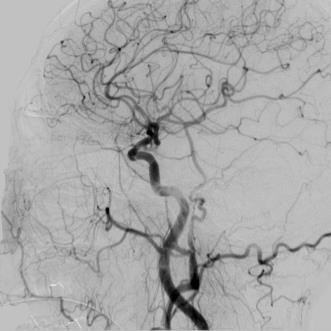

The rapid and accurate direct multi-frame interpolation method for Digital Subtraction Angiography (DSA) images is crucial for reducing radiation and providing real-time assistance to physicians for precise diagnostics and treatment. DSA images contain complex vascular structures and various motions. Applying natural scene Video Frame Interpolation (VFI) methods results in motion artifacts, structural dissipation, and blurriness. Recently, MoSt-DSA has specifically addressed these issues for the first time and achieved SOTA results. However, MoSt-DSA's focus on real-time performance leads to insufficient suppression of high-frequency noise and incomplete filtering of low-frequency noise in the generated images. To address these issues within the same computational time scale, we propose GaraMoSt. Specifically, we optimize the network pipeline with a parallel design and propose a module named MG-MSFE. MG-MSFE extracts frame-relative motion and structural features at various granularities in a fully convolutional parallel manner and supports independent, flexible adjustment of context-aware granularity at different scales, thus enhancing computational efficiency and accuracy. Extensive experiments demonstrate that GaraMoSt achieves the SOTA performance in accuracy, robustness, visual effects, and noise suppression, comprehensively surpassing MoSt-DSA and other natural scene VFI methods. The code and models are available at https://github.com/ZyoungXu/GaraMoSt.